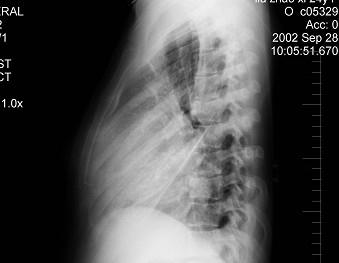

问题 女,24岁,干咳1个月出现胸闷气急,活动时明显,查体颈静脉显露,胸片如图,最可能的诊断为 ( )

选项 A.先天性房间隔缺损 B.心包积液 C.室间隔缺损 D.扩张性心肌病 E.法洛氏四联征

答案 B